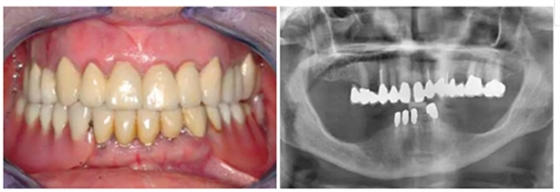

有一位病人因為口腔鱗狀細(xì)胞癌而進(jìn)行了部分舌和口底的切除術(shù),并進(jìn)行了輔助放療。盡管由于組織的纖維化,外科準(zhǔn)備及創(chuàng)口縫合時變的非常困難,但患者的種植手術(shù)最終仍然成功了?;颊吲宕髁肆甑牧x齒,并且一直沒有出現(xiàn)問題。這部分的臨床過程及義齒情況詳見于圖8-18.

圖17& 18:Katharina Dietz-Epple醫(yī)生(Aalen, Germany)完成的冠修復(fù)(上頜)及可摘局部義齒修復(fù)(下頜)。